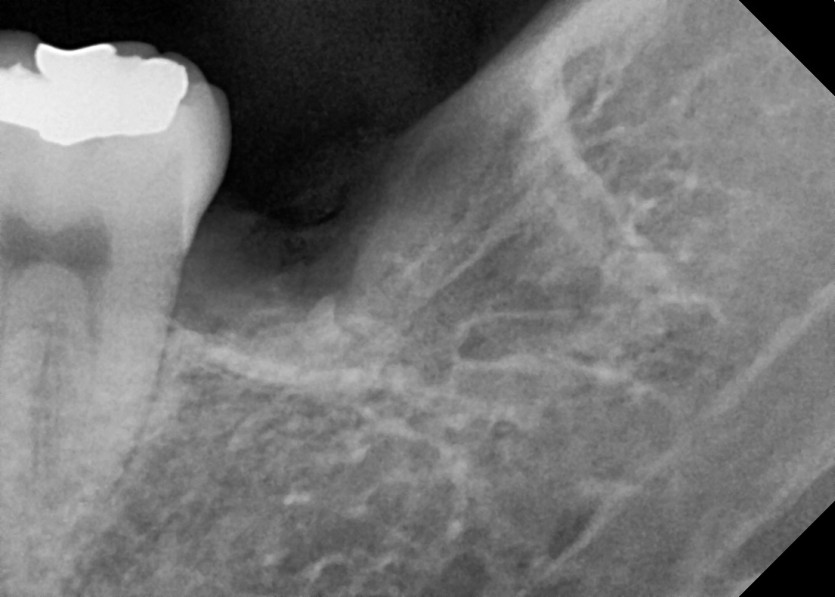

#28,38 사랑니 발치

구강 외과 전문의가 당일 발치했습니다.